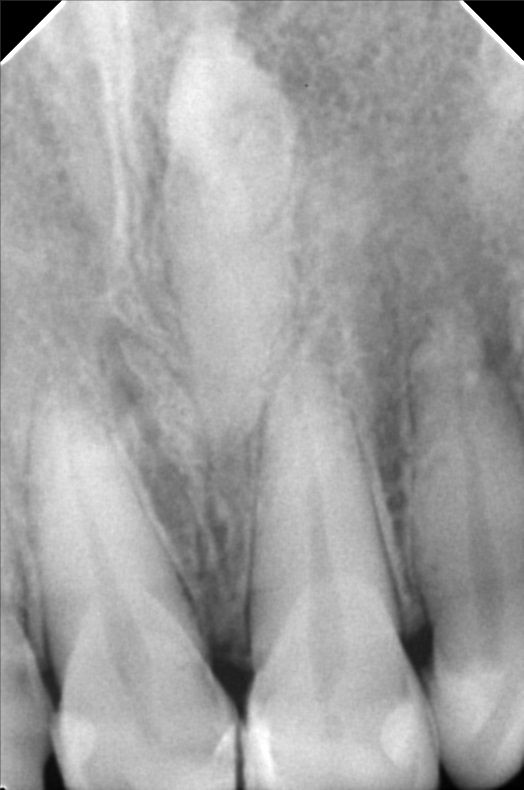

- 10/05/21 -0p/ Lc 11m/21M *22 subject for rct *11 distal repeat lc/ 21 repeat lc/ 12 lingual repeat lc 10/15/21- rct 22mm/ apical abcess laser done apexcal 10/22/21 - LC #12 mesial #11 Lc Distal #21 Distal LC #22 veneer #22 obturate- 22mm guttaflow 04/02/22- veneer due to spaces #41/42/43/31/32/ shade A3/ esthetica 08/25/2023- Cleaning veneer re-polish 11/12/22/21

- bonifacio1.jpg